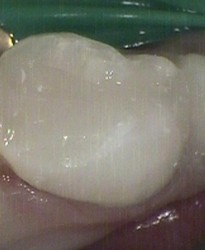

Before ~ incipient (small early) decay After ~ small white filling